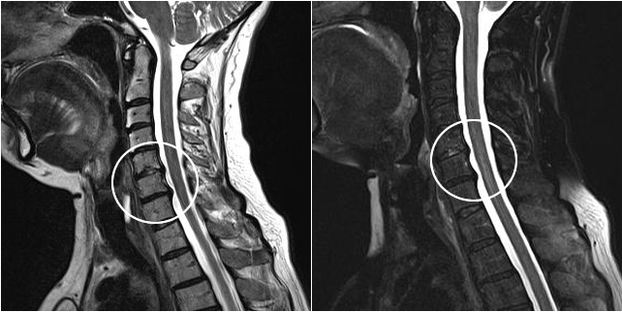

Zu den modernen Diagnosemethoden gehören MRT und CT, die es ermöglichen, die Prozesse der Zerstörung von Knorpel- und Knochengewebe am genauesten zu untersuchen. Außerdem ist es mit dieser Technik bequem, Hernien und andere Weichteildefekte in der Nähe der Krankheitsquelle zu diagnostizieren.

zervikale Osteochondrose im MRT-Bild